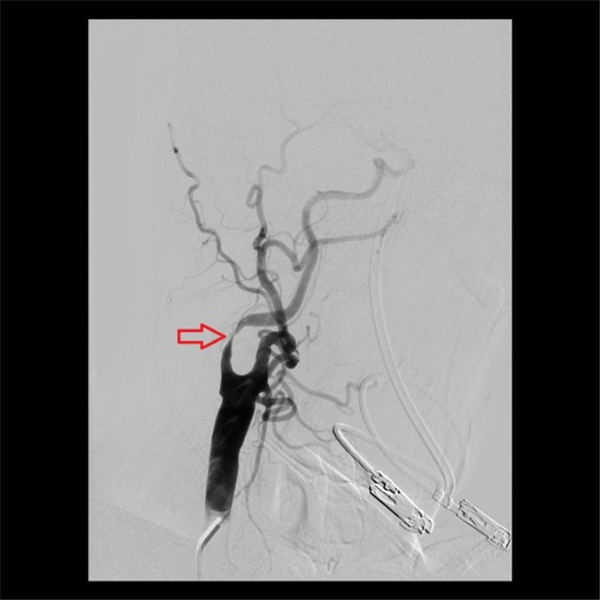

当天,老杜就顺利入住北京燕化医院,第三天就安排了介入手术:在右侧腹股沟局麻之后,穿刺股动脉插管到主动脉,再选择到右侧颈动脉造影,可见右侧颈内动脉重度狭窄、几近闭塞(上图红色箭头)。

术后再次造影显示,右侧颈内动脉支架位置好,膨胀充分,血流通畅,颅内血管未见异常(上图红色箭头所示)。